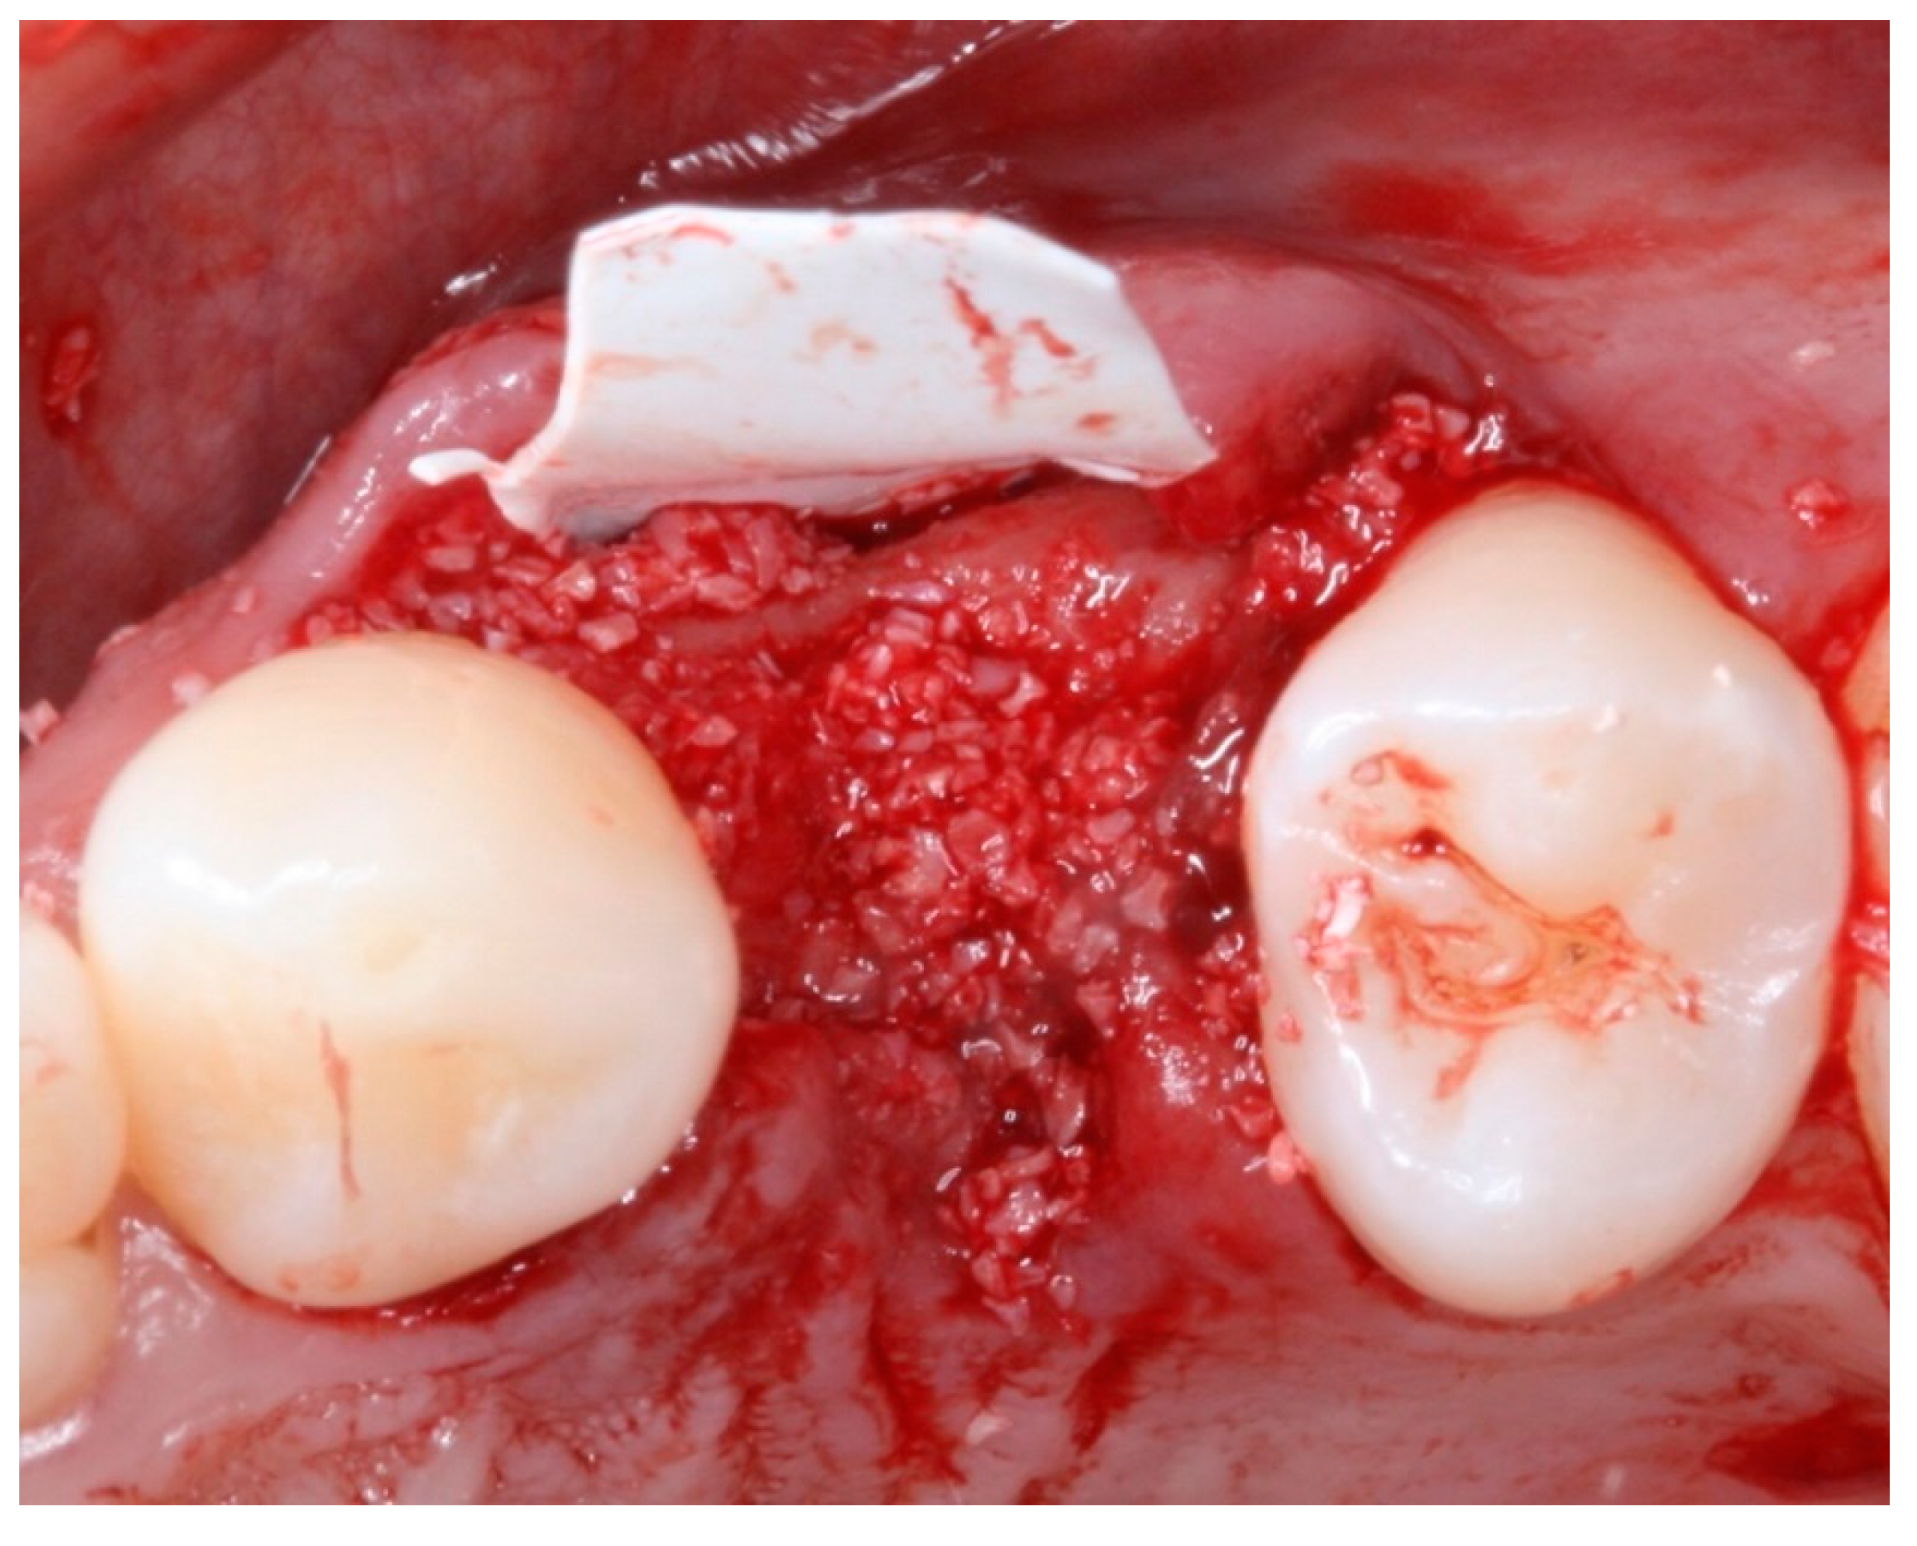

2. Materials and Methods

2.4. Groups

2.5. Post-Surgical Procedures